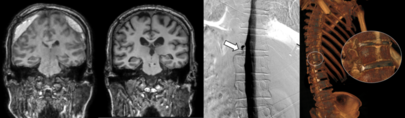

경북대병원 신경외과 조대철 교수 · 고용산 교수 연구팀이 난치성 신경병성 통증, 특히 척추수술 후 증후군(Post-Spinal Surgery Syndrome, PSSS) 환자의 새로운 치료법으로 양방향 내시경(Unilateral Biportal Endoscopy, UBE)을 이용한 최소침습 척수자극술(UBE-SCS)을 제안하고, 그 임상적 안전성과 효용성을 입증한 연구 결과를 국제 학술지에 게재했다고 1일 밝혔다. 연구팀은 기존 대표 치료법인 개방형 척수자극술이 패들 전극의 장점(우수한 전류 전달력·고정력)에도 불구하고, 넓은 절개와 근육 손상으로 인한 수술 후 통증 및 합병증 위험이 존재하는 한계를 극복하기 위해 양방향 내시경 기법을 적용한 새로운 척수자극술을 개발했다. 이번 연구는 2022년부터 2024년까지 척추수술 후 증후군 환자 14명을 대상으로 후향적 분석을 시행했으며, 수술 시간, 통증 지수(VAS), 기능장애지수(ODI), 합병증 발생률 등을 종합적으로 평가했다. 또한 수술 중 신경감시(MEPs, SSEPs)를 적용해 시술 안전성을 확보했다. 그 결과 평균 내시경 수술 시간이 단축되고, 시술 성공률(영구 자극기 삽입) 92.8%를 달성했다. 하